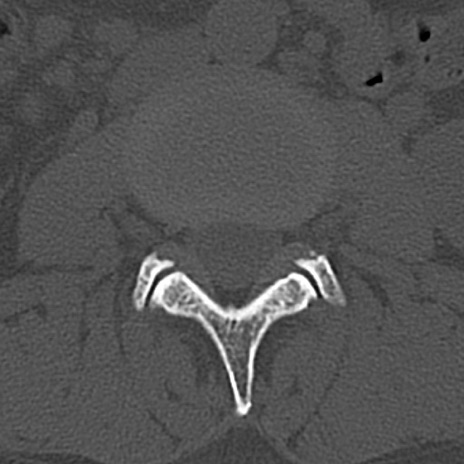

腰椎CT

横断像と矢状断像